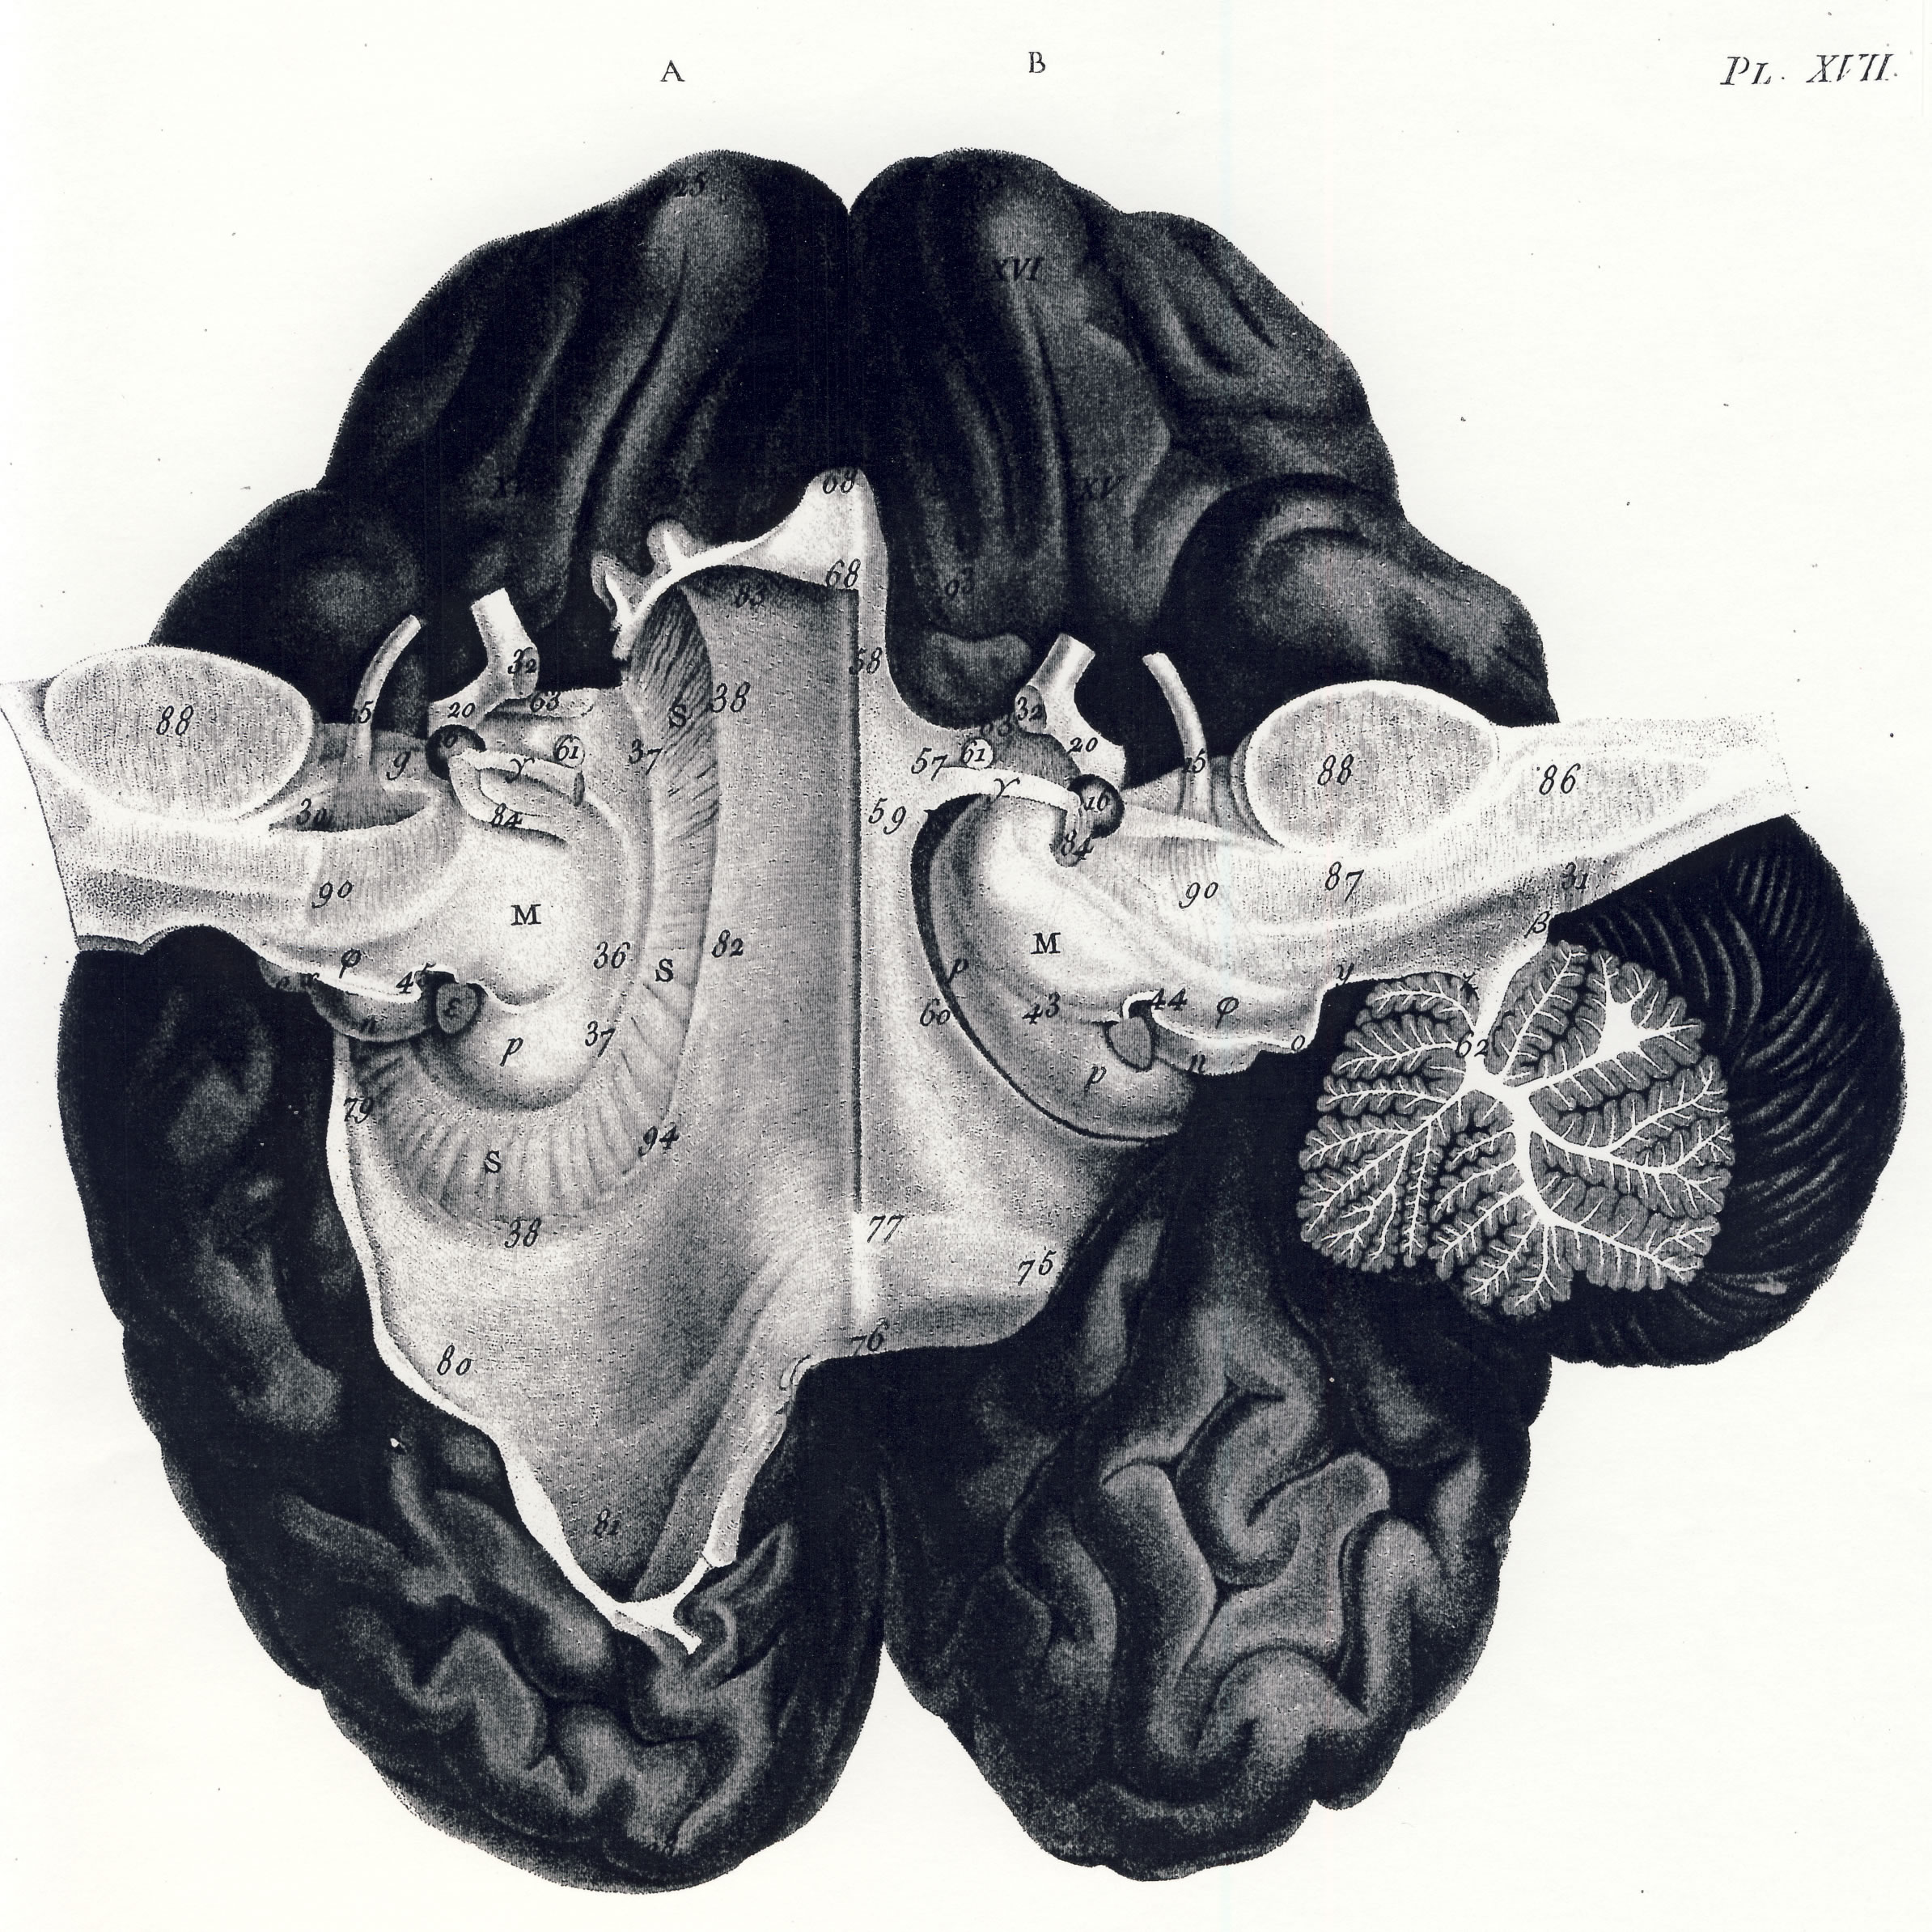

Gall, F. J. (1818). Anatomie et physiologie du système nerveux en général, et du cerveau en particulier, Avec des observations sur la possibilité de reconnoître plusieurs dispositions intellectuelles et morales de l´homme et des animaux, par la configuration de leurs têtes.

Librairie Grecque-Latine-Allemande, Vol. 3, I-XXXV u. 1-379 100 planches.